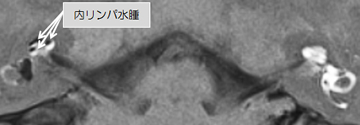

メニエール病に対する内リンパ水腫画像診断

めまいを繰り返したり、難聴が変動するメニエール病の原因は「内リンパ水腫」と言われています(図2)。当科では実際に内リンパ水腫を生じているのかを画像で可視化することによって判断する検査を臨床研究として行っております(図3)。方法は鼓膜に麻酔を行った後、経鼓膜的に鼓室内へ造影剤を注入し、24時間後に3.0テスラMRI撮影(高分解能)を行います(1泊2日)。